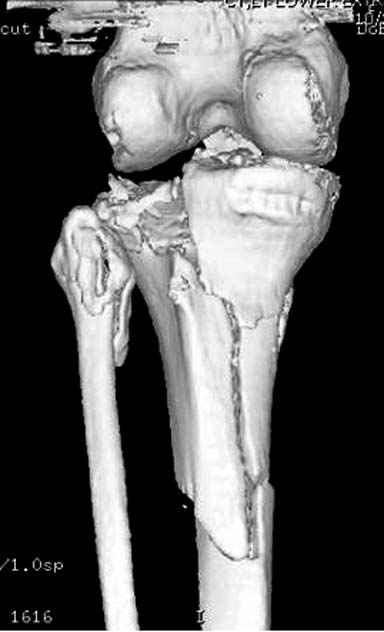

Для адекватной оценки необходимо предоставить хотя бы по две проекции до и после синтеза. Снимки после синтеза - с захватом всей длины сегмента т.к. использовался гвоздь. По предоставленной одной некачественной проекции сказать можно только сказать что и решение, и результат спорные.

Отдельные переломы тибиал плато и перелом проксимальной трети большеберцовой кости отличаются от переломов тибиал плато с вовлечением диафиза. Здесь перелом тибиал плато типа Schatzker VI, полученный в результате высокоэнергетической травмы. Перелом метафиза образовал отрыв суставной поверхности от диафиза с вовлечением медиального и латерального мыщелков. Двухмыщелковые переломы из-за укрочения опасны развитием компартаментального синдрома, повреждением латерального мениска и связок.

И так, высокоэнергетическая травма – это, прежде всего, тяжёлое повреждение мягких тканей со сломанной костью внутри. Относится ли данное утверждение к переломам плато? И да, и нет. Значительная часть наших пациентов с переломами плато – это люди пожилого и старческого возраста с низкоэнергетической травмой. Как правило, это низкоэнергетические повреждения с отсутствием контузии, фликтен, то есть хорошим состоянием мягких тканей, где в результате перелома нарушена, прежде всего, механическая ось конечности. Мягкие ткани позволяют оперировать нам такие переломы в ранние сроки. Но, главная проблема, с которой мы сталкиваемся здесь – это проблема фиксации порозной кости. Вот здесь и уместны блокируемые имплантаты (благо, в отличие от нашей работы 10-15 лет назад, сейчас и продукта данного, и производителей на рынке предостаточно в разном ценовом диапазоне). Имплантаты прежних генераций здесь используются с трудом, нужно хорошо знать классическую технику, пользоваться пластикой, не забывать о том, что банальный костный цемент может быть реальной «палочкой-выручалочкой». Но, в нашем случае – другая история. Это высокоэнергетическая травма. И здесь как раз сломанная кость внутри повреждённых мягких тканей. Здесь как раз и доступы, и время, подходящее для операции, и технологии – всё сплетается в один клубок, распутать который нам и помогает нормальный предоперационный план. И так, в случае высокоэнергетического перелома тибиального плато мы сталкиваемся с тяжёлым повреждением мягких тканей, контузиями, фликтенами, риском развития компартмент-синдрома, зачастую переломы носят открытый характер и в своих крайних составляющих сопровождаются повреждением и сосудов, и нервов. Поэтому вначале мы лечим мягкие ткани – то бишь создаём комфортные условия для них. Это может быть шинирующий наружный фиксатор, это может быть и более многими любимый аппарат Илизарова. Условие одно – избегать гипердистракции, это плохо для мягких тканей и даже может способствовать развитию компартмент-синдрома. Мягким тканям должно быть «уютно» в этот непростой для всей конечности период и беспокоить их лишний раз в это тяжёлое время не нужно. Иногда – а это зависит от структуры перелома, стабильности отломков и тяжести повреждения мягких тканей даже хорошо смягчённая, в положении лёгкого сгибания в коленном суставе, очень свободная внешняя повязка сгодится – полимерная или даже гипсовая. Иногда – только дисциплинирующее лёгкое скелетное вытяжение. Главное, если нет компартмента – не трогай! Ждём. И стараемся оперировать в оптимальные сроки, диапазон которых здесь достаточно широк – от 5-6 до 21-23 дней с момента травмы. Морщинки на коже лучше всего подскажут нам это время. Однако, время впустую не теряем – мы обследуем больного и, не побоюсь этого слова, думаем даже, и обсуждаем с нашей бригадой пре-план. Что нам нужно из обследования? КТ – идеально. Однако, что скрывается за утверждением: «КТ – золотой стандарт в обследовании всех пациентов с внутрисуставными переломами»? Ведь то, что перелом, в основном, виден и на банальной рентгенограмме – аксиома. Так вот КТ нам нужна, прежде всего, для адекватного пре-планирования. Для того, что бы решить, какой доступ использовать, что и как репонировать, где и какой имплантат разместить. Срезы – фронтальные, сагиттальные, но, прежде всего, поперечные срезы плато важны. Я приложил файл с фрагментом моей лекции “Approaches to the Proximal Tibia”, что я делал для мастер-курса в Давосе в том году. Прошу прощения за самоцитирование, но что-то уникальное сейчас не представляется возможным подготовить. Так вот, там, где-то ближе к началу, слайд с подробным объяснением того, что мы ищем и как мы можем использовать поперечный срез. Какой фрагмент остался интактным и стабильным, то есть к чему мы всё будем привязывать, где импрегнированная часть кости и нужна ли будет пластика, где идут линии перелома и как нам правильно рассчитать доступ (ы), что бы они прошли как раз над линией перелома аккурат для «открытия данной книги». Ведь одних только доступов для тибиального плато не менее десятка и значительную часть из них, за исключением разве что артроскопического в той или иной комбинации можно использовать в данном случае. Такое планирование делает возможным миниинвазивную хирургию даже при суставных переломах. Естественно, если понимать под миниинвазивностью не только и не столько размер мягкотканого окна, а тот дополнительный вред, который наши манипуляции даже через маленький разрез могут нанести мягким тканям и кости. Именно такое изучение КТ даёт нам представление и о том, - сколько, каких имплантатов и как использовать при каждом конкретном переломе. Нет КТ? Дело хуже. Но трагедии так же нет, ведь и там где она есть, что-то непрерывно ломается, дозаказывается, ожидается и так далее. В этом случае выручают косые рентгенограммы. Под какими углами и сколько – вам решать. Финально, изучая все классические и косые срезы, мы должны сформировать ясную мысленную 3Д картину перелома. Это и поможет нам в выборе имплантатов и их расположения, в том, нужна ли будет пластика, или нет. Конечно, Вы, Владимир, правы, в последнее время наблюдается определённая тенденция менее частого, что ли, использования пластики при внутрисуставных переломах. Связано это с массовым применением пластин новых образцов от разных производителей, но с одной идеологией. Практически полностью отказались от использования пластики при переломах проксимального плеча и дистального луча. Многие не делают этого при переломах пятки (я - делаю). Но вот при импрессии части плато… Ведь пластика – это не заполнение «дырки», это профилактика вторичного смещения столь нагружаемого участка сустава. Если вы можете применить «рафтинг» тонкими блокированными винтами, это ещё может быть оправданным, хотя, повторюсь, я не рискую. Но без него???

Согласен с постами докторов Кульджанова и Волны. В данном случае мы не отмечаем признаков тщательного предоперационного планирования, что сказалось на характере принятого решения и его результате. В нашей клинике, мы бы использовали длинную блокированную пластину по латеральной поверхности, через проксимальное окно отрепонировали бы суставную поверхность, через дистальное фиксация 3-4 винтами в с/3 б/берцовой кости. По медиальной поверхности в качестве поддержки - 1/3 трубчастая или реконструктивная пластина. С большой долей вероятности использовали бы костную аутопластику.